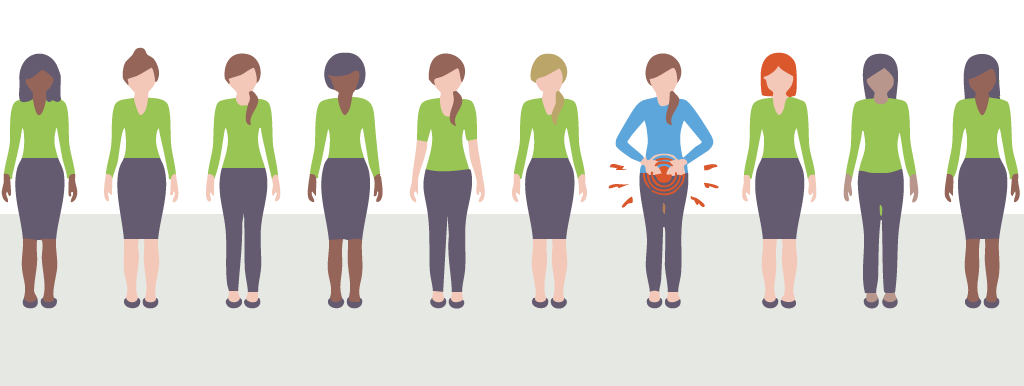

Voedingsaanpassingen verlichten pijnklachten bij een groot deel van de vrouwen met endometriose. Dat blijkt uit de grootste wereldwijde studie ooit naar het effect van voeding en supplementen op endometriose, uitgevoerd door de Universiteit van Edinburgh. Vooral het verminderen van alcohol, gluten, zuivel en cafeïne blijkt effectief.